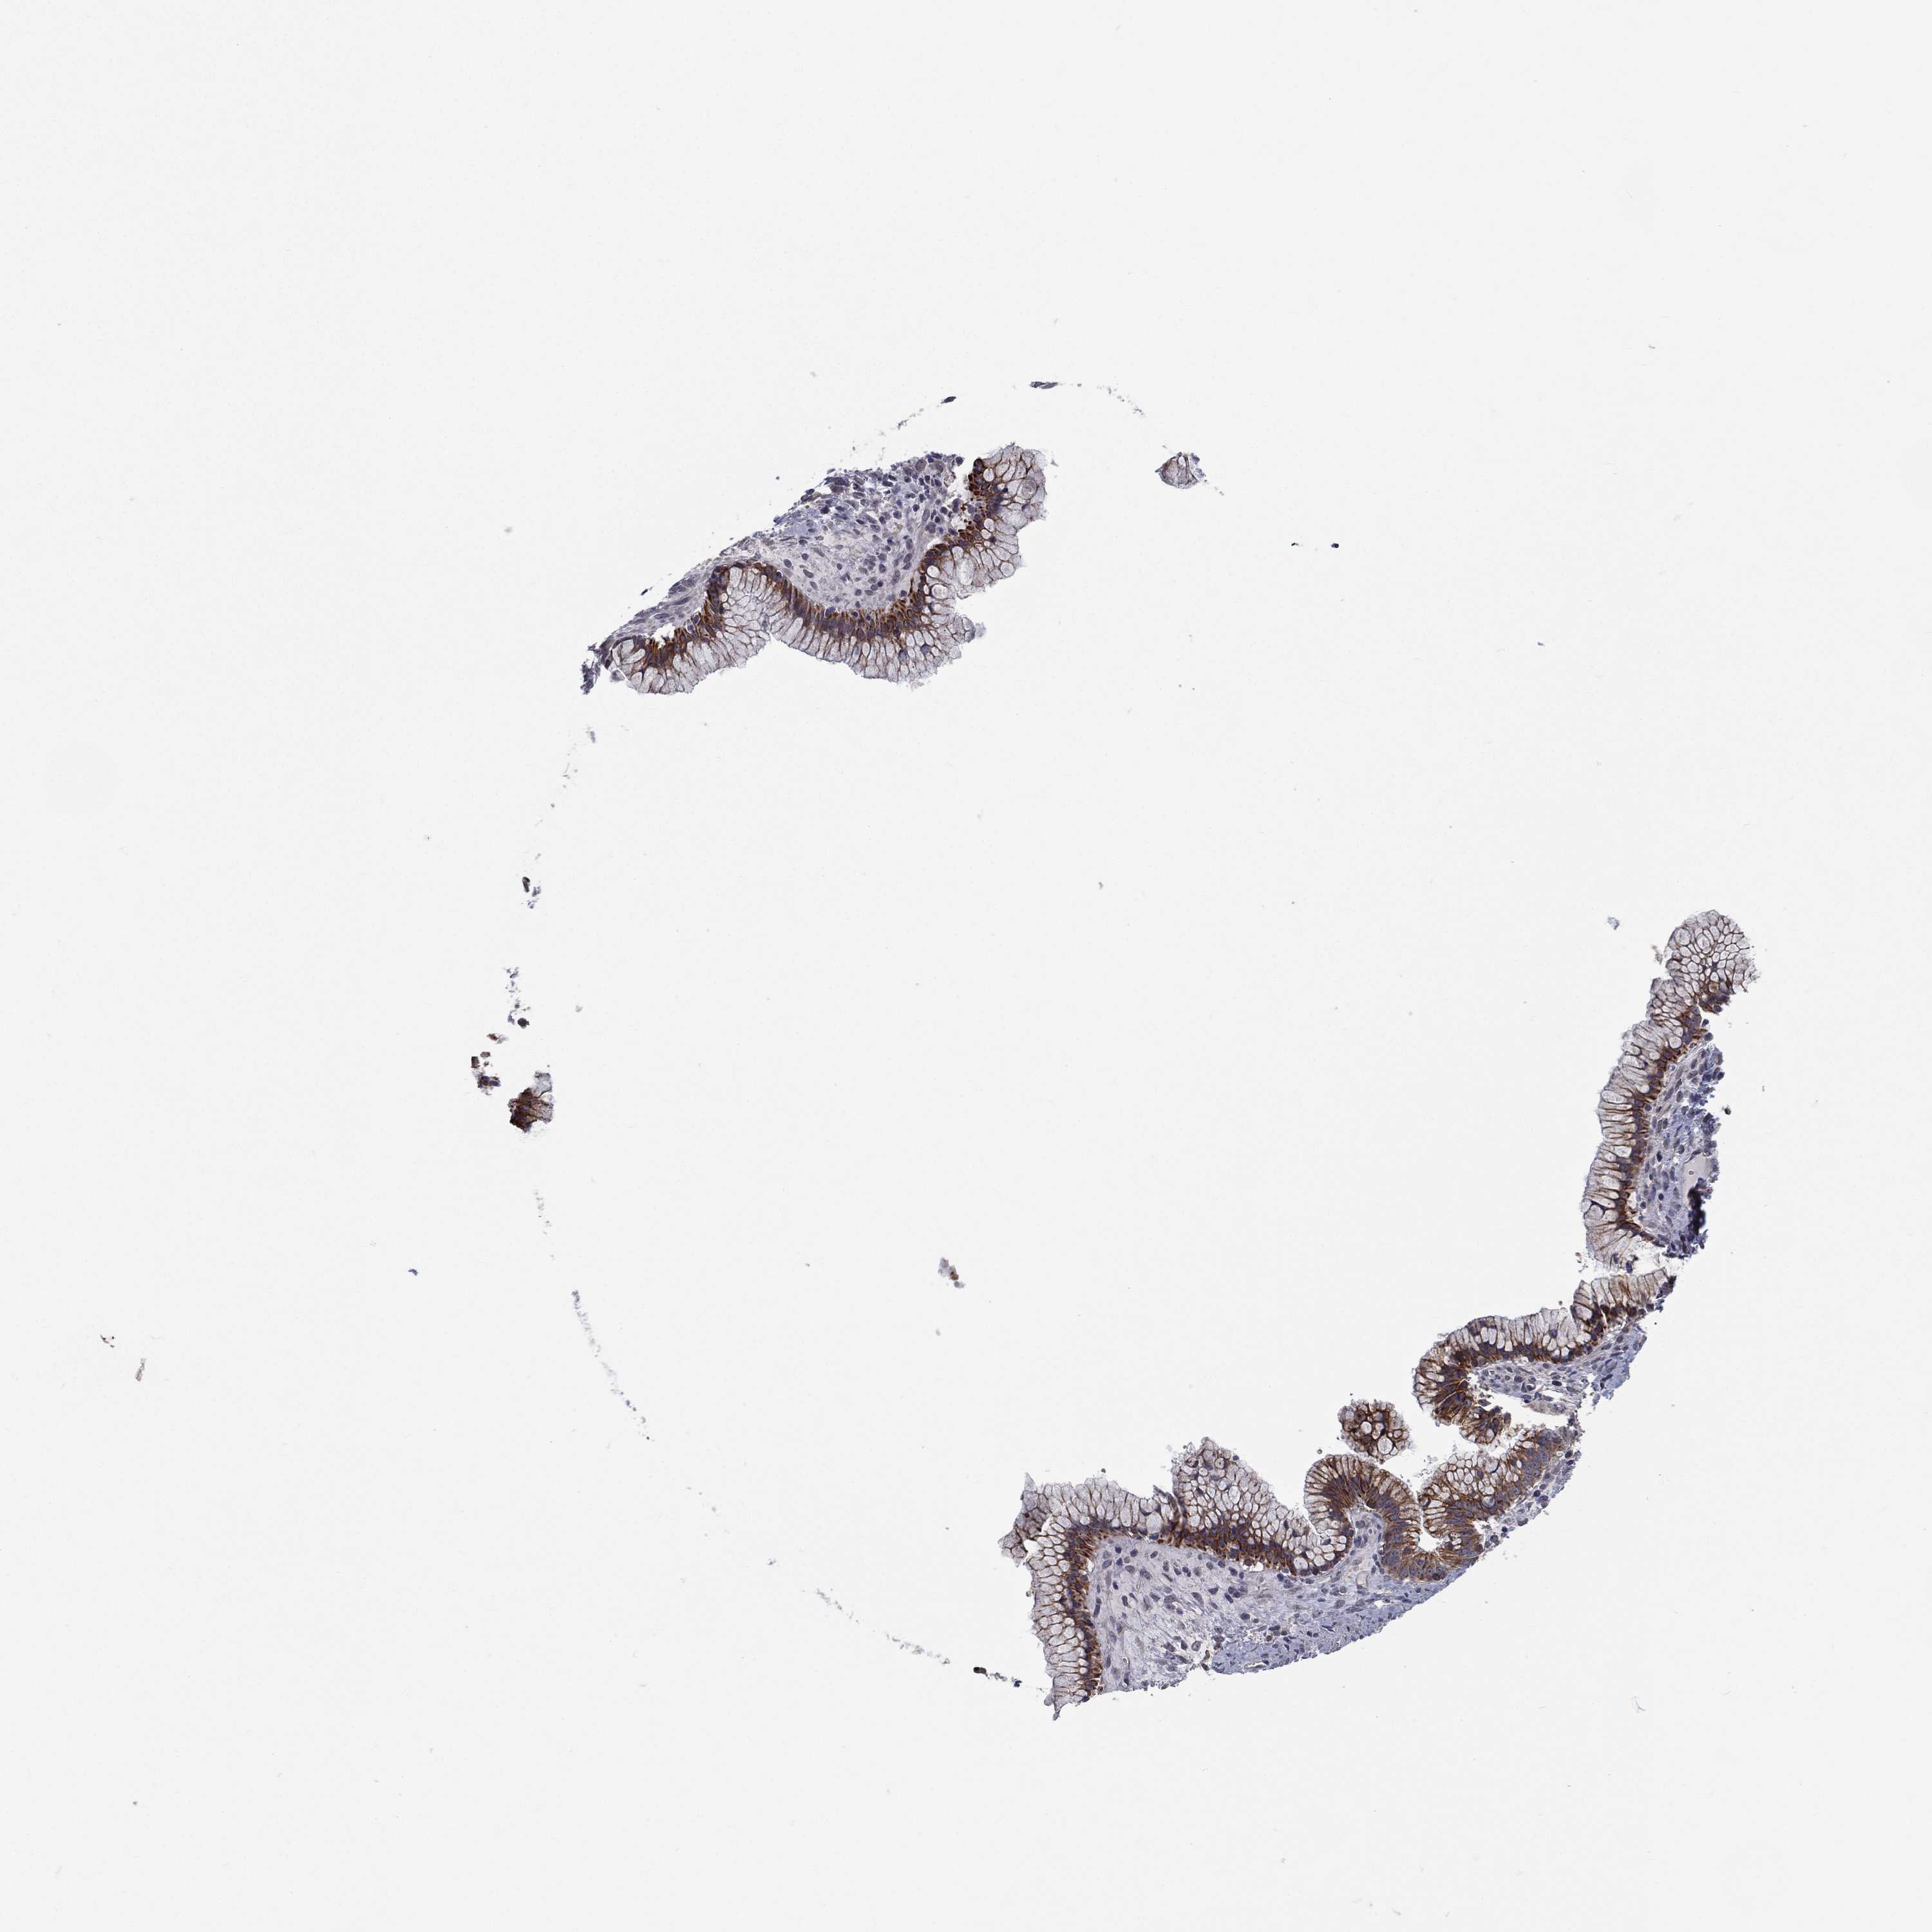

OVARIAN CANCER - Protein expressioni

A mouse-over function shows sample information and annotation data. Click on an image to view it in a full screen mode. Samples can be filtered based on level of antibody staining by selecting one or several of the following categories: high, medium, low and not detected. The assay and annotation is described here.

Note that samples used for immunohistochemistry by the Human Protein Atlas do not correspond to samples in the TCGA dataset.

Antibody stainingi

Antibody staining in the annotated cell types in the current human tissue is reported as not detected, low, medium, or high, based on conventional immunohistochemistry profiling in selected tissues. This score is based on the combination of the staining intensity and fraction of stained cells.

Each image is clickable and will lead to virtual microscopy that enables deeper exploration of all samples and also displays staining intensity scores, fraction scores and subcellular localization as well as patient and tissue information for each sample.

Antibody HPA041412

Antibody HPA056006

Cystadenocarcinoma, serous, NOS

Carcinoma, endometroid

Cystadenocarcinoma, mucinous, NOS

Carcinoma, NOS